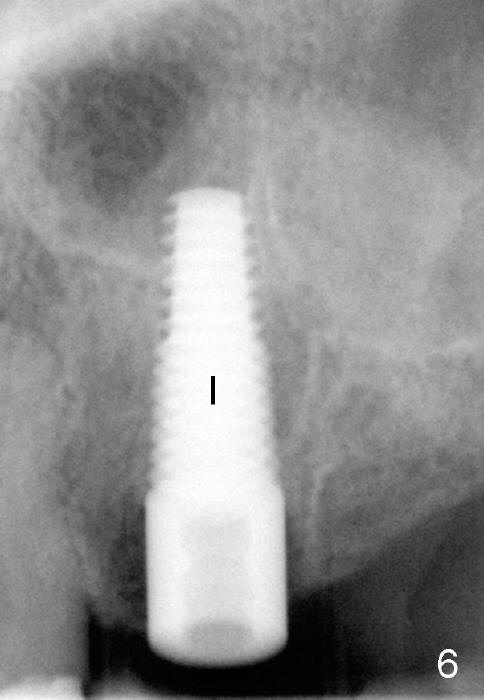

A 47-year-old lady has lost an upper left bridge (Fig.4,7). She is a dental phobic, but is concerned about cosmetics. Immediate implant and immediate provisional for the 1st bicuspid are easily accepted. There is a sinus septum above. Intraop PAs show that 4.5x17 mm tap (Fig.5) and 5x17 mm implant (Fig.6, insertion torque > 60 Ncm) are placed mesial to the septum without sinus membrane perforation. An abutment is placed immediately and an immediate provisional is fabricated.